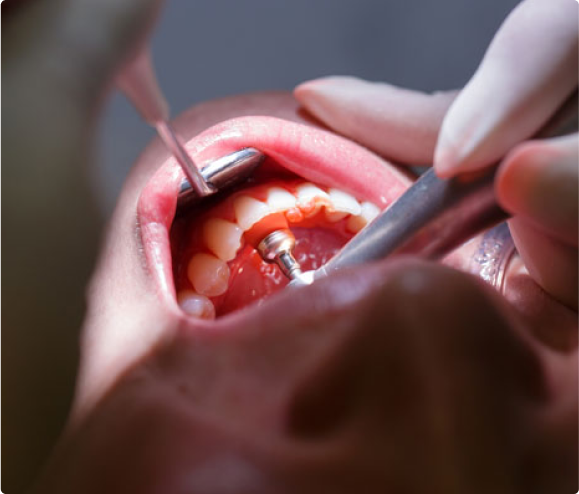

• Next, get a proper cleaning. The most common first stage treatment is a Deep Cleaning or Scaling and Root Planning which involves the removal of plaque and calculus deposits both above and below the gum line.

• Patients with more advanced periodontal disease may be referred to a Periodontist (Gum Specialist) for further evaluation and treatment that may include gum and/or bone surgeries.